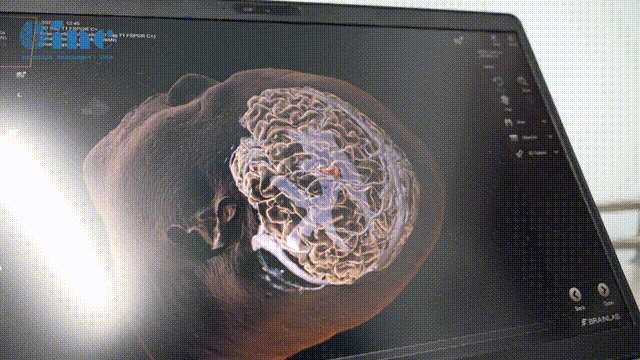

嘀、嘀、嘀、嘀、嘀……看似普通的笔状神经导航棒在头上各个位置轻点,竟然能神奇的看穿颅内的一切。这名脑深部海绵状血管瘤患者的大脑完整的展现在屏幕上,红色的肿瘤跃然纸上,连肿瘤的位置、形状及和周围功能区神经纤维束的关系都可以清楚的看见。由于肿瘤位于功能区,手术采用了术中神经导航技术,为安全手术保驾护航。

▼巴教授利用术中神经功能导航精准定位肿瘤

功能区手术使用术中导航已经成为巴教授示范教学手术中的常态。导航系统犹如赐予神经外科医生一双透视眼,让医生在术中可以即时标定病变范围,实现精确定位,让肿瘤无处遁形,大大提高手术及检查的准确性、安全性。在术中开颅状态下,患者可以进行数次术中核磁检查,肿瘤切没切干净,还有多少残留,一清二楚,医生可以根据检查结果随时调整手术方案,继续切除,直至肿瘤彻底清除干净。